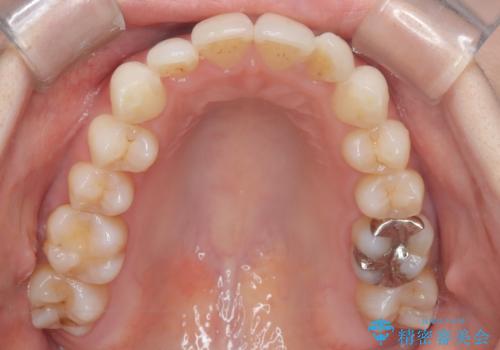

矯正後の後戻りで前歯にガタツキができてしまった インビザラインで改善

- 子どものときにワイヤー矯正をしていたが、後戻りによって前歯のガタツキが気になってきたとのことで来院されました。

アライナー矯正希望だったため、インビザラインによる治療を行いました。